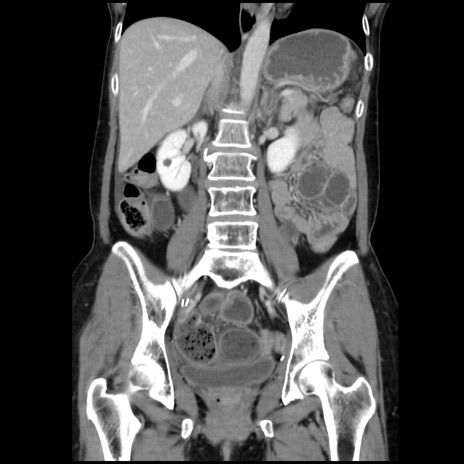

症例32(冠状断像)

【症例】40歳代 女性

【主訴】上腹部痛、嘔気・嘔吐

【現病歴】約9時間前頃から急に上腹部痛、嘔気、嘔吐が出現。改善しないため救急要請。

【既往歴】子宮頚癌(広汎子宮全摘術、放射線療法)、腸閉塞

【身体所見】腹部:平坦、軟、腸雑音亢進、上腹部を中心に腹部全体に圧痛あり。

【データ】WBC 8400、CRP 0.03